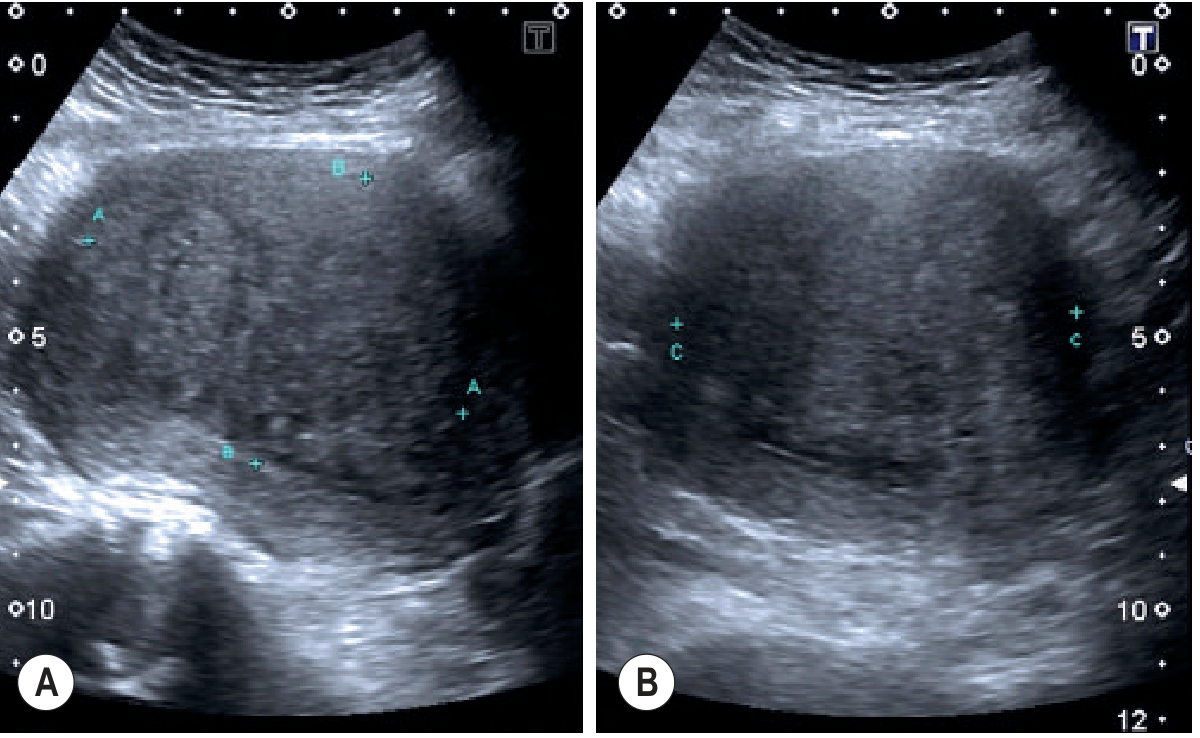

| Myometrial cysts (2–6 mm) | Direct | High |

| Subendometrial echogenic striations | Direct | High |

| Heterogeneous myometrium | Direct | Moderate |

| Blurred endomyometrial interface | Direct | Moderate |

| Fan/rain-shower shadowing | Direct | Moderate–High |